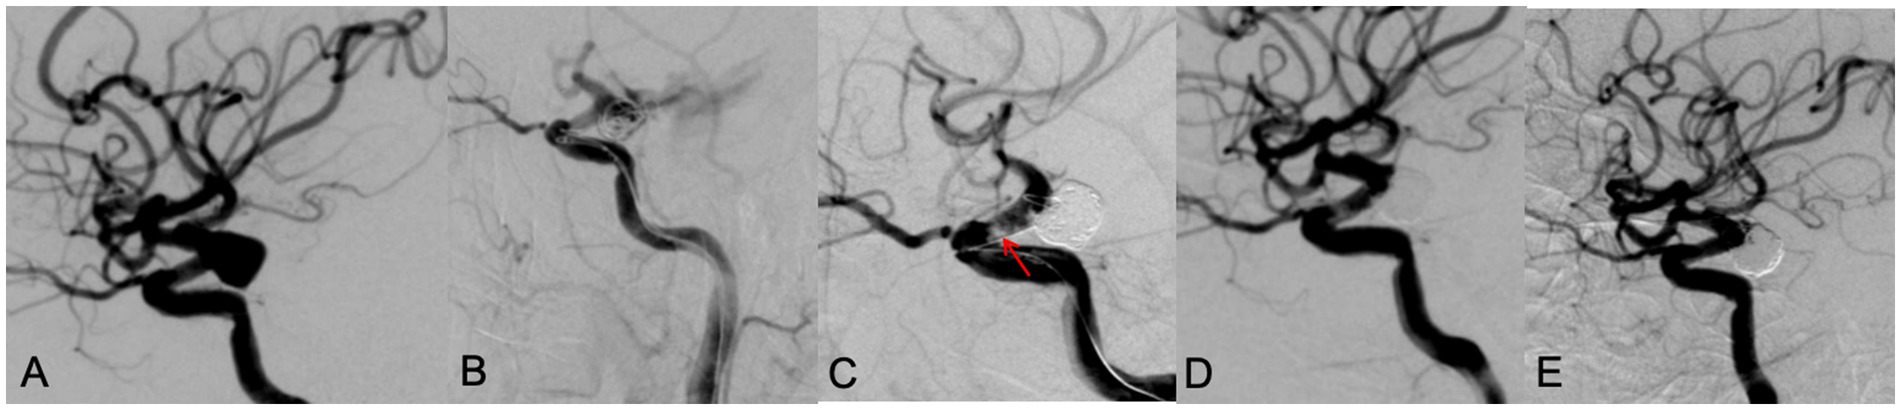

Intraoperative complications occurred in two patients, both of them were in the LVIS group. One patient had a left posterior communicating artery aneurysm. During the procedure, the aneurysm ruptured. Immediately, emergent protamine reversal of heparin was applied, and multiple ev3 coils were packed through another microcatheter until angiography showed no contrast extravasation, however, an in-stent thrombosis was noted. Tirofiban was then administered. The final angiography showed patent vessels, disappeared in-stent thrombosis, and occlusion of the aneurysm (Figure 3). The patient recovered well. The second patient had a left vertebral artery wide-neck aneurysm. During LVIS stent-assisted embolization, the aneurysm ruptured. Rapid coil packing was performed, and as contrast extravasation persisted, finally the parent artery and the aneurysm were all occluded. Because of the patent contralateral vertebral artery, the patient recovered well postoperatively.

Figure 3. A 65 year old male patient with diplopia for 3 weeks. DSA showed a left posterior communicating aneurysm with wide neck (A). During the LVIS stent assisting embolization, the aneurysm ruptured with contrast leakage (B). After rapid dense coil packing, contrast leakage was stopped, however, an in-stent thrombosis (red arrow) was observed (C). After intravenous use of tirofiban, thrombosis disappeared, the aneurysm was occluded with MRRC grade 1 (D). A 9 months’ follow-up DSA examination showed the aneurysm was occluded well with MRRC grade 1 (E).